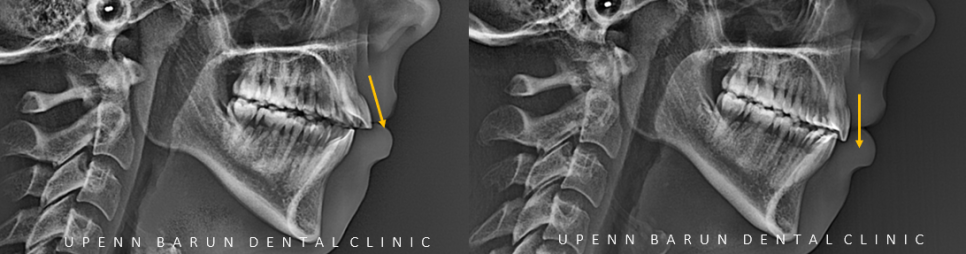

ceph before & after

교정 전엔 앞니가 뻐드려져 각도가 나와 있었는데요,

교정이 끝나고 앞니의 각도가 개선되어 안모의 변화 뿐만 아니라 앞니의 외상 위험성도 줄일 수 있습니다.

어금니 교합과 앞니의 교합이 모두 안정적인 상태로 바뀌었습니다.

교정 전에는 아랫입술이 뻐들어진 위에 치아에 눌려 돌출되어 보였으나,

각도가 개선되면서 환자의 코부터 윗, 아랫 입술까지 조금 더 자연스럽게 연결되어 보입니다.